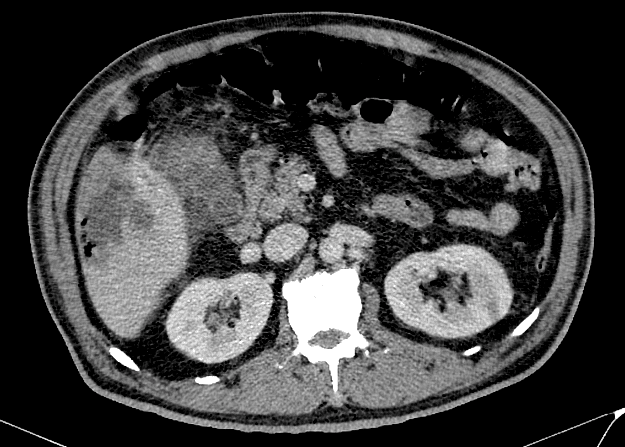

Viêm túi mật

» Thông tin: Nam giới – 60 tuổi.

» Lâm sàng: Đau bụng cấp.

# Viêm túi mật cấp biến chứng vỡ => Apxe gan.